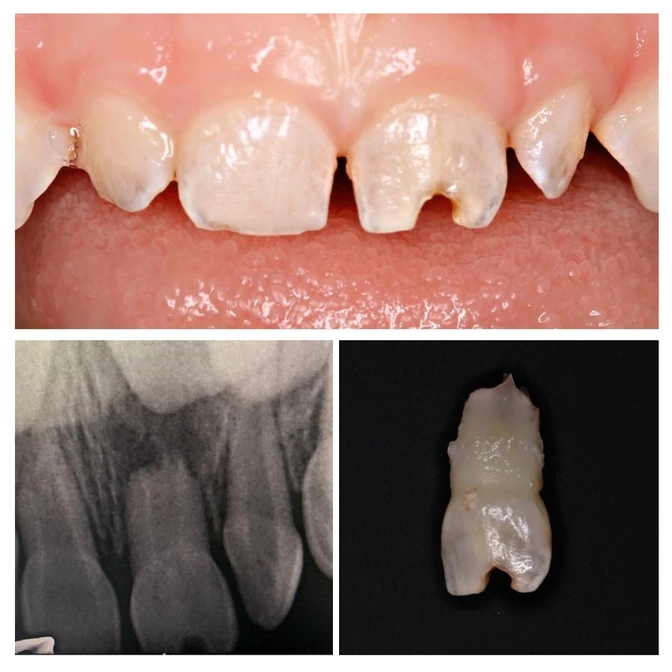

Год назад ребенок получил травму центрального резца.

Сейчас ему три года и родителей очень смущала эстетика.

Назначен рентген и что мы видим - зуб надо удалять!

Посмотрите на снимок.

Имеется очаг воспаления.

Началось патологическое рассасывание корня.

Это прямая угроза зачатку постоянного зуба!